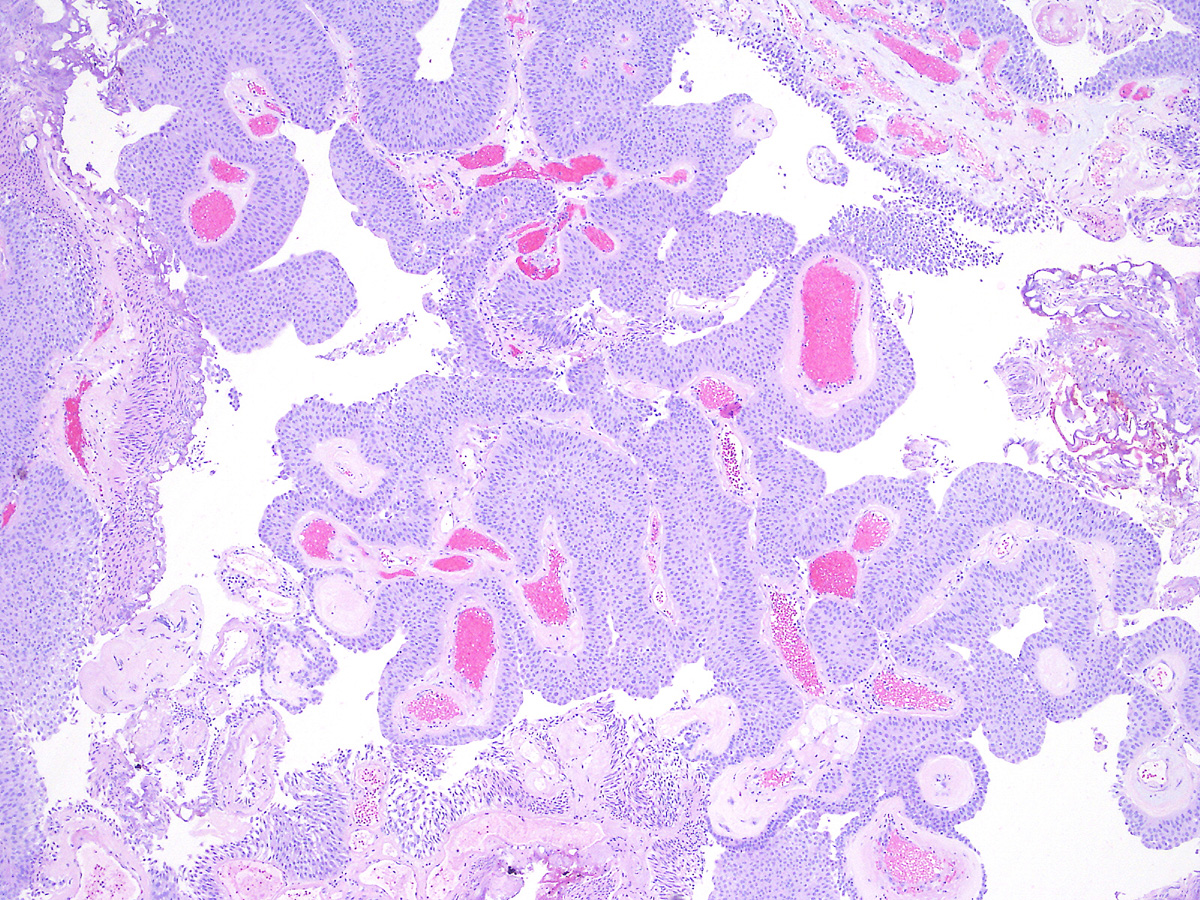

Consensus grade: Low-grade papillary urothelial carcinoma (LG-PUC)

A 74 year-old woman underwent a TURBT.